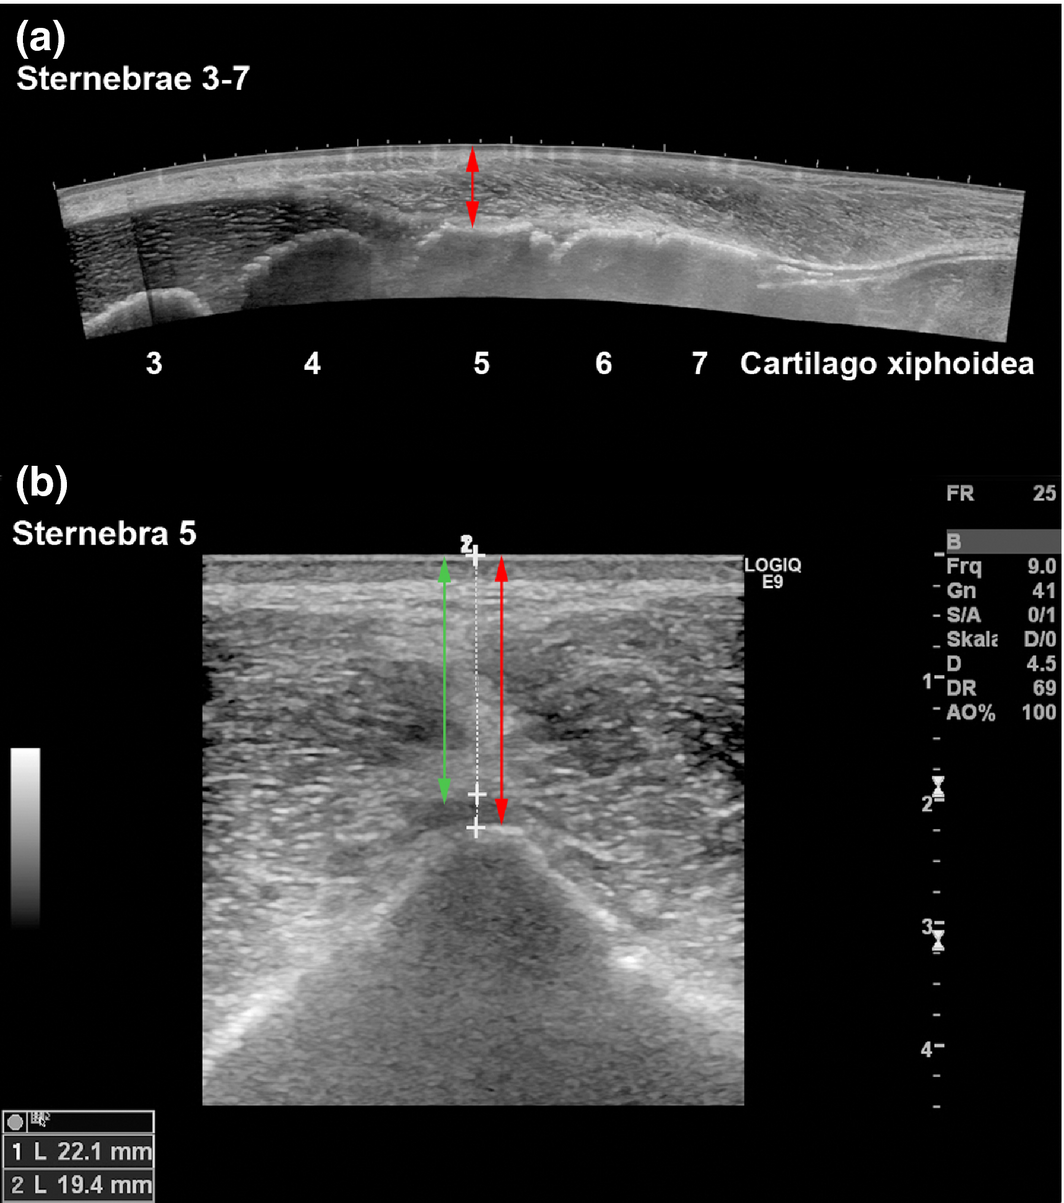

Figure 1.

Ultrasonograms of the equine sternum, horse 18 (Mare, 5 years). (a) Longitudinal panoramic image (LOGIQview function). The ventral bony margins of the sternebrae 3–7 are clearly visble. The red arrow indicates the distance between sternebrae 5 (ventral bony margin) and the skin. (b): Transverse B-mode image of sternebra 5. Skin-to-cartilage distance (green double arrow, 19.4 mm) and skin-to-bone distance (red double arrow, 22.1 mm).

Bone marrow aspiration

The ventral contour of each sternebra could be clearly detected during ultrasonography (Fig. 1), which allowed determination of the distance between the skin surface and the ventral bony margin of the sternebrae. The mean distance between skin and sternebra measured 26.4 ± 6.4 mm for sternebra 4 and 29.6 ± 7.8 mm for sternebra 5. The use of injection needles to indicate the positions of sternebrae 4 and 5 (Fig. 2) resulted in a correct positioning of the Jamshidi needle to aspirate bone marrow from a sternal insertion depth of 10 mm or 30 mm.

In both, sternebra 4 and sternebra 5, bone marrow aspiration was always feasible at a calculated sternal insertion depth of 30 mm. In sternebra 5, bone marrow aspiration was also feasible at a calculated sternal insertion depth of 10 mm. In sternebra 4, bone marrow aspiration from 10 mm insertion depth was successful in only 2 out of 12 cases.

Depth of the puncture canal

The skin-sternebra distances determined by measurements on cCT images were compared to ultrasonographic measurements. Distances determined by ultrasonography were constantly shorter, for sternebra 4 (6.3 ± 5.8 mm) and for sternebra 5 (8.9 ± 4.5 mm). The sternal insertion depth calculated during bone marrow aspiration and the actual insertion depth measured on cCT images differed constantly. For sternebra 4, the calculated insertion depth was in almost all cases underestimated by approximately 9.0 ± 5.5 mm. For sternebra 5, the calculated insertion depth was also constantly underestimated, but by approximately 2.9 ± 2.0 mm. The puncture canal deviated from an exact ventro-dorsal orientation in the median plane but was always placed within the sternebrae.